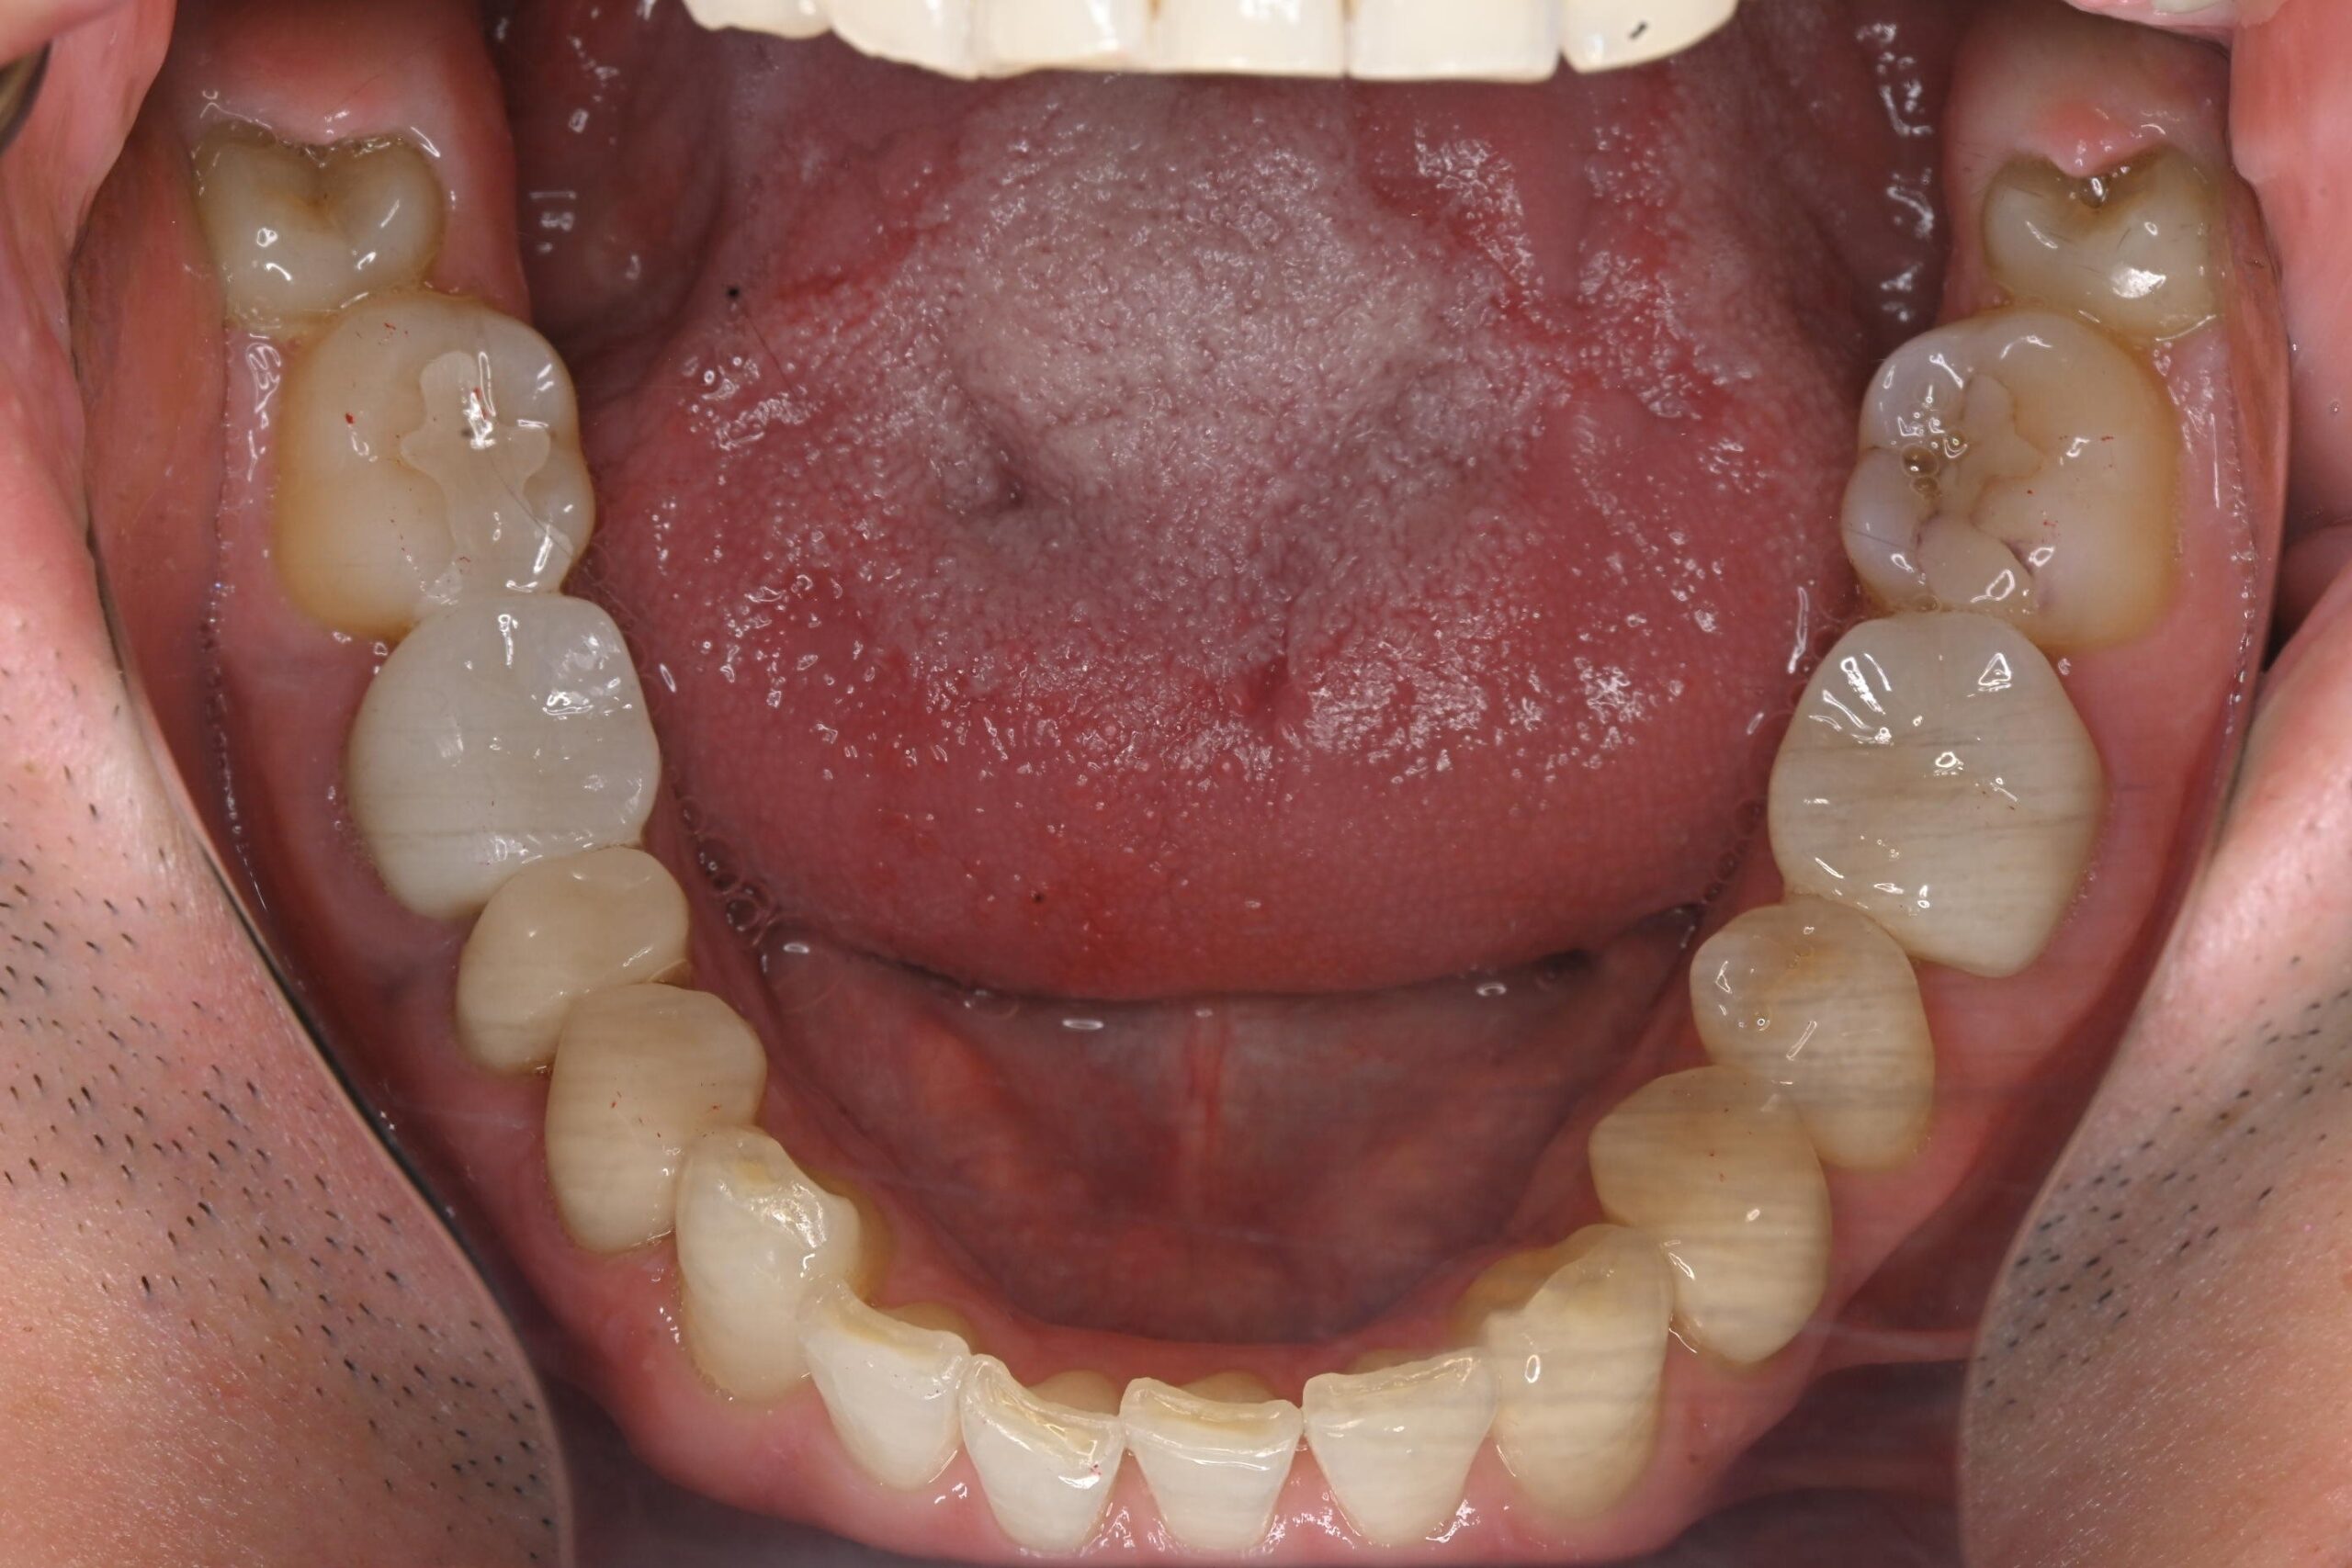

初診時の口腔内の状態:

口腔内には多数の銀歯(銀合金)が確認されました。患者様は過去に多くの虫歯治療を受けており、そのほとんどが保険適用内の銀合金で修復されていました。

患者様はパッチテストによりニッケルなどに対するアレルギーを持っていることが確認されており、口腔内の銀合金もアレルギーの原因となっている可能性が高いと診断しました。また、レントゲン画像を確認すると、被せ物や詰め物の内部、あるいは隙間から、虫歯(カリエス)や根の細菌感染が疑われる状態も確認されました。